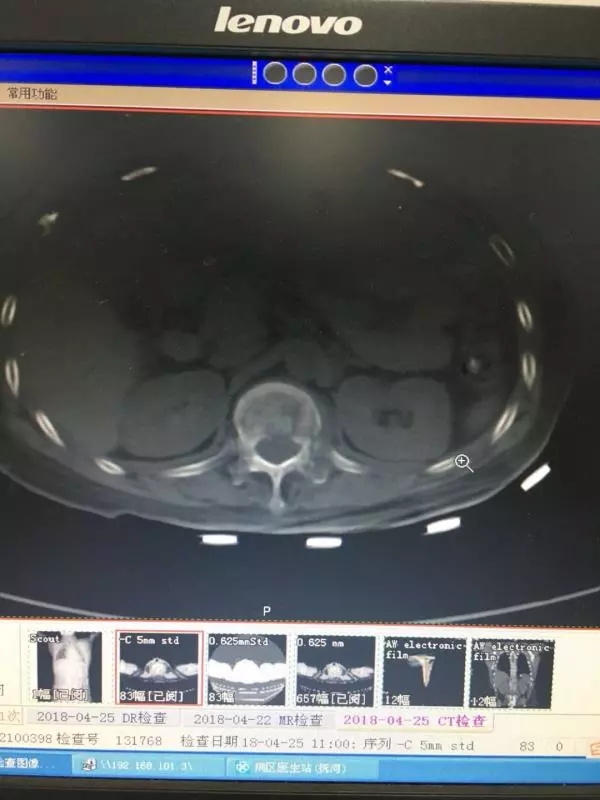

经皮椎弓根螺钉同样也是通过经皮做一小切口,利用C臂机作为医生的眼睛,依次进入导针,扩孔,后期进入椎弓根螺钉。操作稍有不慎,螺钉就可能进入椎管内,造成截瘫。如下图所示: